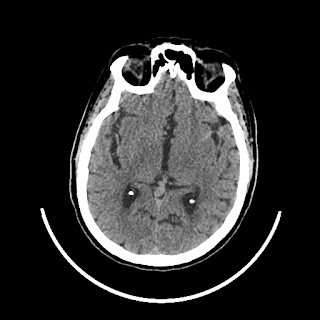

A 75 years old woman with DM-2 since 3 years

Patient O/E images:

C/O: Breathlessness X 2-3 day's

Vomiting 1-2 episode since last night

Cough X 2-3 day's

H/O: unconsiouness since few hour's at home around 10:30 pm

K/C: DM / HTN since 2-3 year's